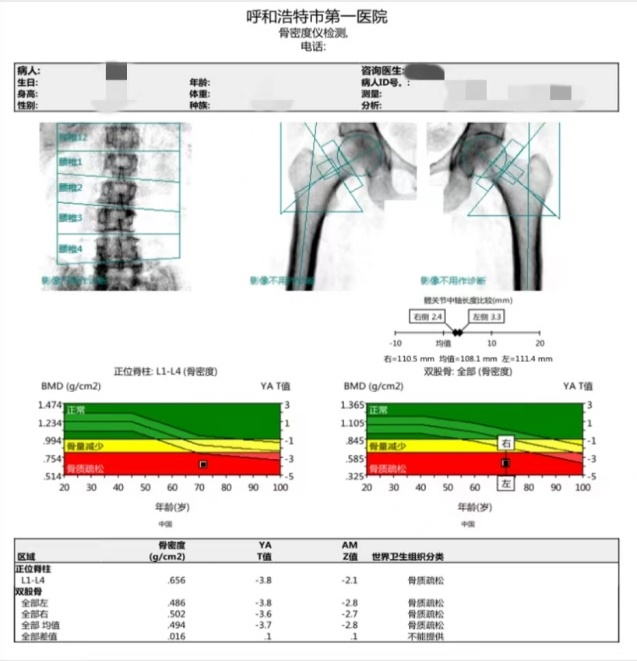

医生说:经过核医学科DXA骨密度测量,您正位脊柱和双股骨T值均≤-2.5,诊断为骨质疏松。

目前临床上普遍应用的骨密度检查技术叫做双能X线吸收法(Dual-energyX-ray Absorptiometry,DXA),这也是临床骨质疏松检查的“金标准”。其使用两种不同能量的X射线进行检查,由于不同能量的X线穿透不同密度的人体组织所衰减的程度不同,通过计算机处理射线衰减信息就可以很好地区分测量人体骨骼与软组织的组织含量和密度了。